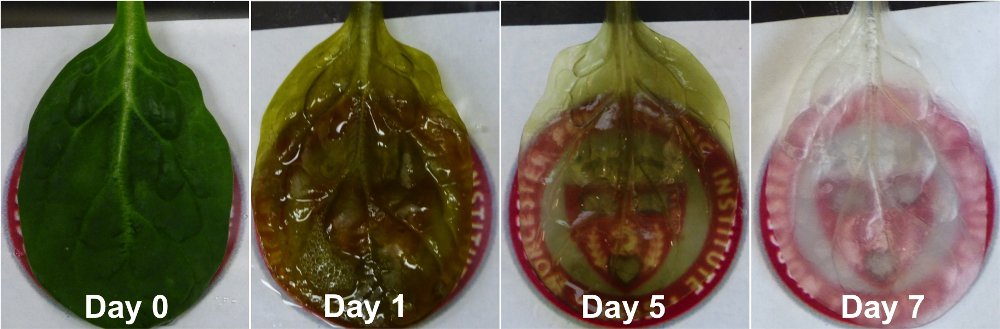

為應付心臟移植的需求,科學家一直致力研究培養出心臟組織的方法,惟心臟血管脈絡錯綜複雜,難以完整地「複製」出來,以致培養出來的心臟組織難以提供輸血的關鍵功能。美國有科學家日前成功將靜脈網絡與人類心臟血管非常相似的菠菜葉,製作成具功能性的心臟組織,望能助心臟病患者修復心臟。

菠菜葉的靜脈網絡與人類心臟血管相似,故美國伍斯特理工學院的科學家嘗試利用菠菜葉轉化成心臟組織,解決一直以來培育心臟組織未能持續輸血的問題。

科學家首先用洗潔精除去菠菜葉上的植物細胞,將菠菜葉變成透明,及後將與人類血液細胞相似的液體及微珠注入菠菜葉的靜脈中,令血管成形。

研究人員表示,研究成果令人鼓舞,但仍然有很多需要解決的問題,「暫時都未清楚如何將植物的靜脈系統與人類心臟血管整合在一起,以及人類身體會否產生排斥反應。」